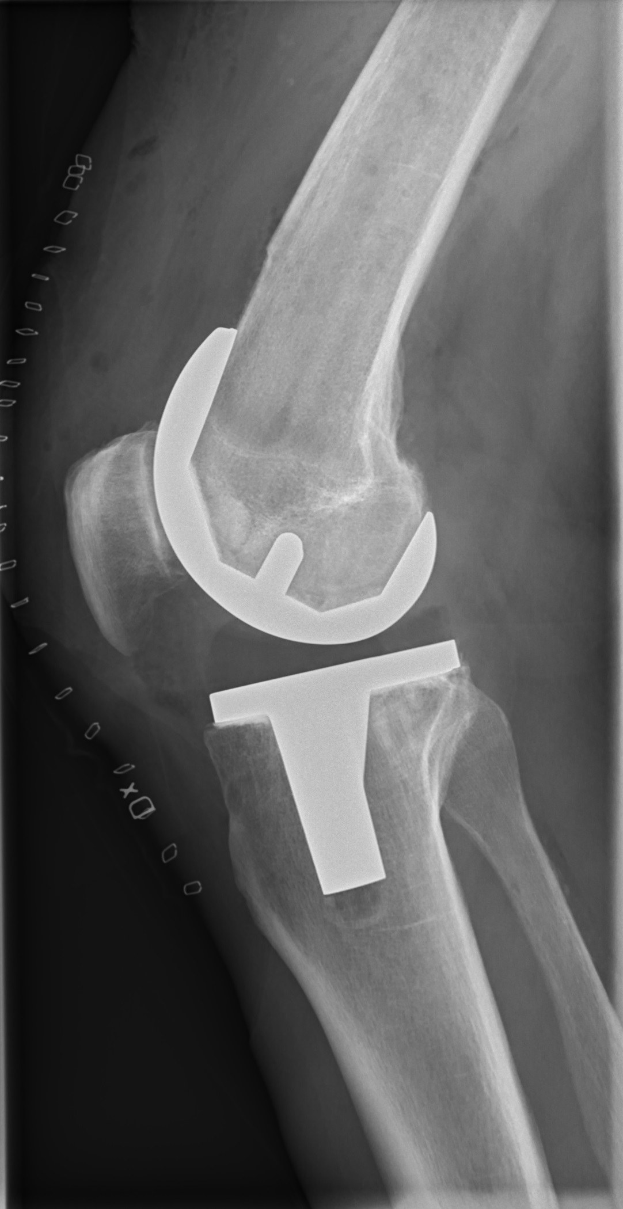

Der niederländische Innenverteidiger wird sich nun einer Operation unterziehen, um den Schaden zu beheben. Sein Ausfall hinterlässt beim FC Augsburg eine Lücke – der Verein muss für längere Zeit auf seinen erfahrenen Kapitän verzichten und die Defensive umstellen.